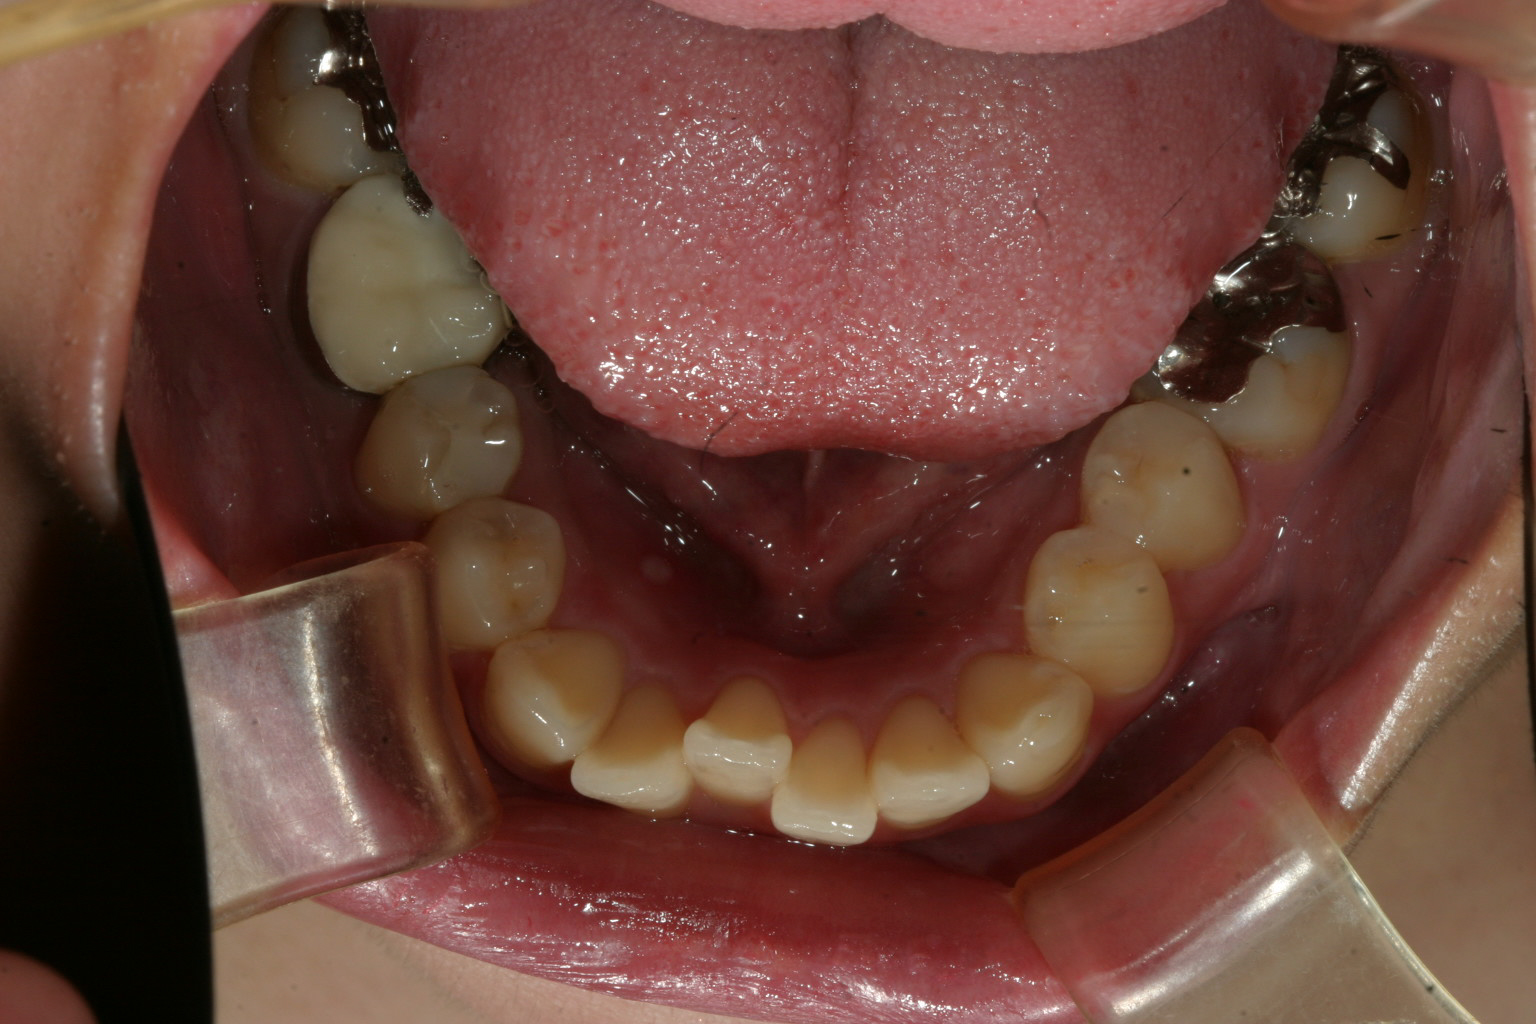

下顎歯並びがガタガ タ前歯のねじれ 出っ歯も気になる。

下顎は結構ガタガタが有ります。